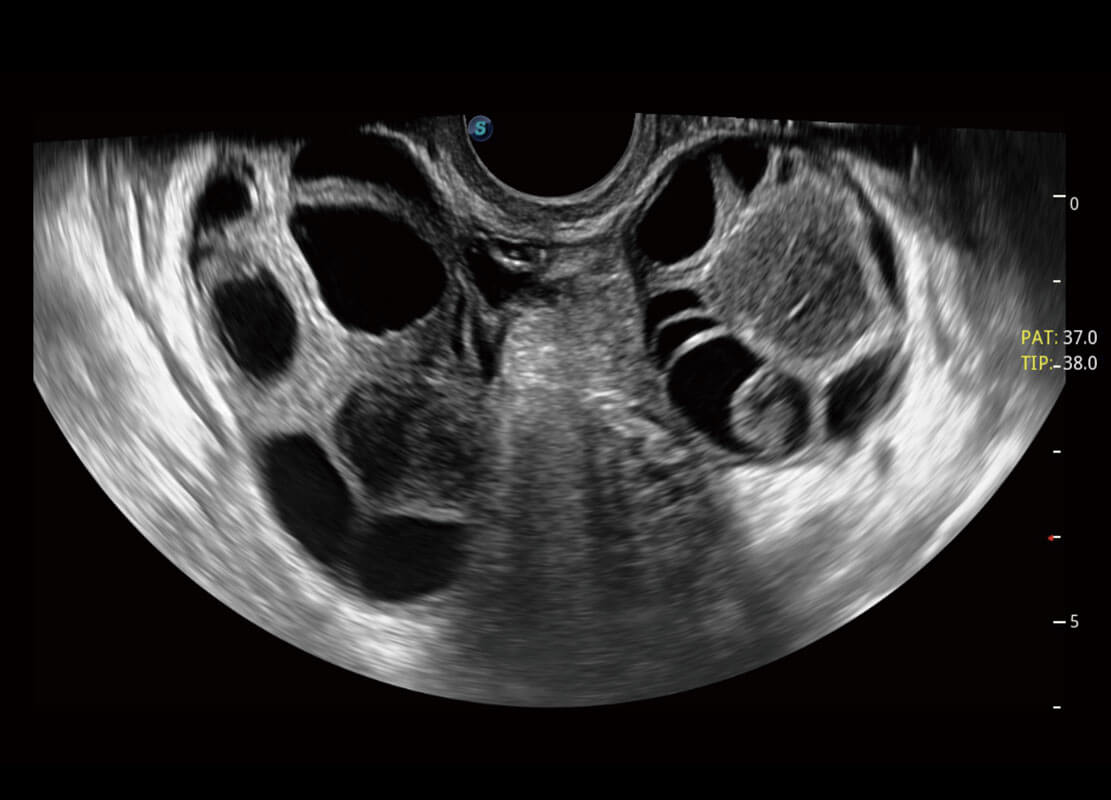

P60優(yōu)異的圖像質(zhì)量搭載專(zhuān)科探頭,在婦科基礎(chǔ)疾病的診斷、卵泡生長(zhǎng)的監(jiān)測(cè)、輸卵管通暢情況的判別等方面為您提供生殖應(yīng)用方案。

腔內(nèi)婦科-卵巢